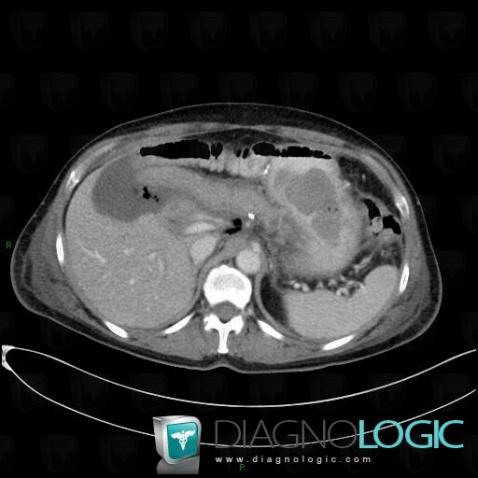

Biloma, Liver, CT

Here is the specific information in the key image above:

- Diagnosis Biloma, Location(s) Liver, with gamuts Low density in portal phase hepatic lesion, Cystic hepatic lesion